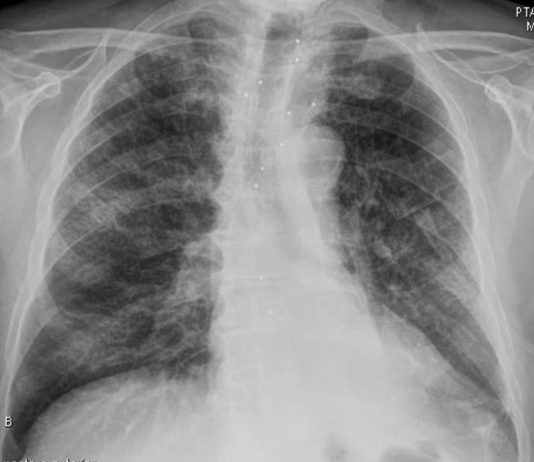

73-year-old female

patient with fever and respiratory distress.